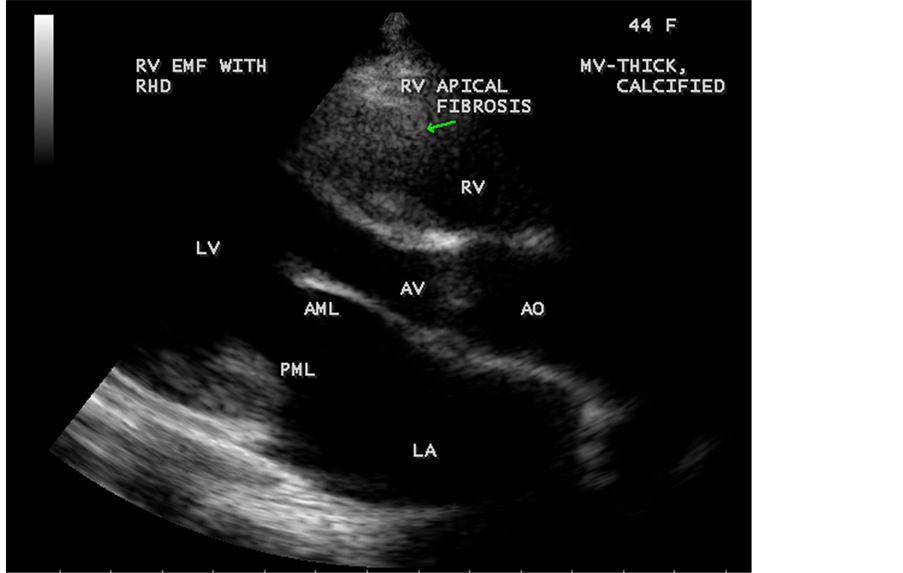

Figure 54. RV EMF with Rheumatic mitral valve involvement in a 44-year-old female―Paras- ternal long axis view. Mital valve (AML―anterior mitral leaflet, PML―posterior mitral leaflet) is thickenned and calcified.

Figure 55. RV EMF with Rheumatic mitral valve involvement in a 44-year-old female-apical four chamber view.

Endomyocardial Fibrosis may present as dilated cardiomyopathy in a child as shown in Figure 37 and Figure 38 [34] . In some cases, scattered areas of fibrosis in the submitral and subtricuspid regions (subvalvular fibrosis) as shown in Figure 43 and may cause valvular regurgitation. The valvular regurgitations occur in rheumatic heart disease and the differential features are given in Table 2. It may coexist with RHD (rheumatic heart disease) rarely as shown in Figure 28, Figure 54, Figure 55 and Figure 63 [35] .

ventricle”) in a 16-year-old female as shown in Figure 50 to Figure 53 were detected. RV EMF with rheumatic involvement of mitral valve as shown in Figure 54 and Figure 55 in a 44-year-old female and in Figure 63 in a 55-year old female. Biatrial enlargement due to rheumatic atrioventricular (AV) valves (mitral and tricuspid) involvement characterized by stenosis of the valves are illustrated in Figure 56 to Figure 59 in a 54-year-old female and it is differentiated from EMF which is characterized by AV valve regurgitation as shown in Figure 34 and Figure 60. RV EMF associated with thickening and fibrosis of moderator band in a 16-year-old female was shown in Figure 46. RV EMF associated with apical left ventricular hypertrophic cardiomyopathy was shown in a 47-year-old male as in Figure 61 and in a 65-year-old female as in Figure 62.